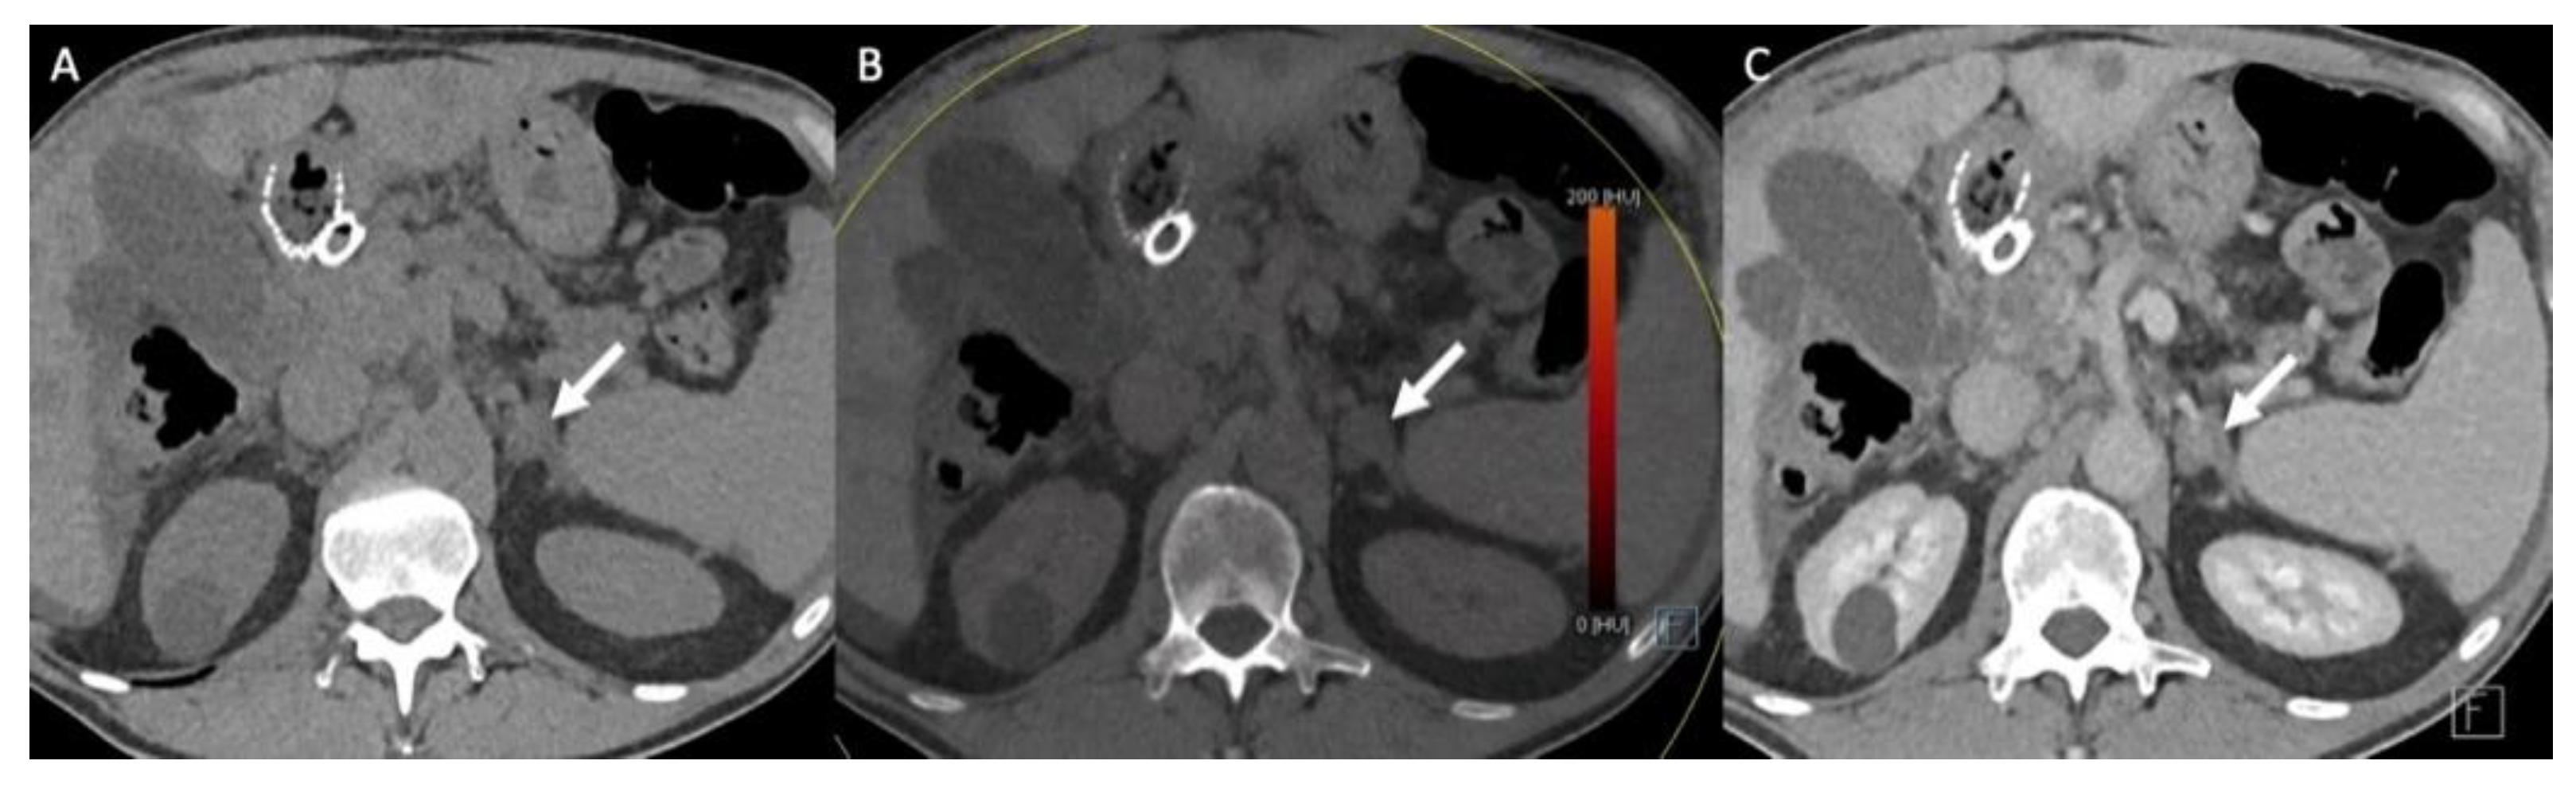

- Nagayama, Y.; Inoue, T.; Oda, S.; Tanoue, S.; Nakaura, T.; Ikeda, O.; Yamashita, Y. Adrenal Adenomas versus Metastases: Diagnostic Performance of Dual-Energy Spectral CT Virtual Noncontrast Imaging and Iodine Maps. Radiology 2020, 296, 324–332. [Google Scholar] [CrossRef]